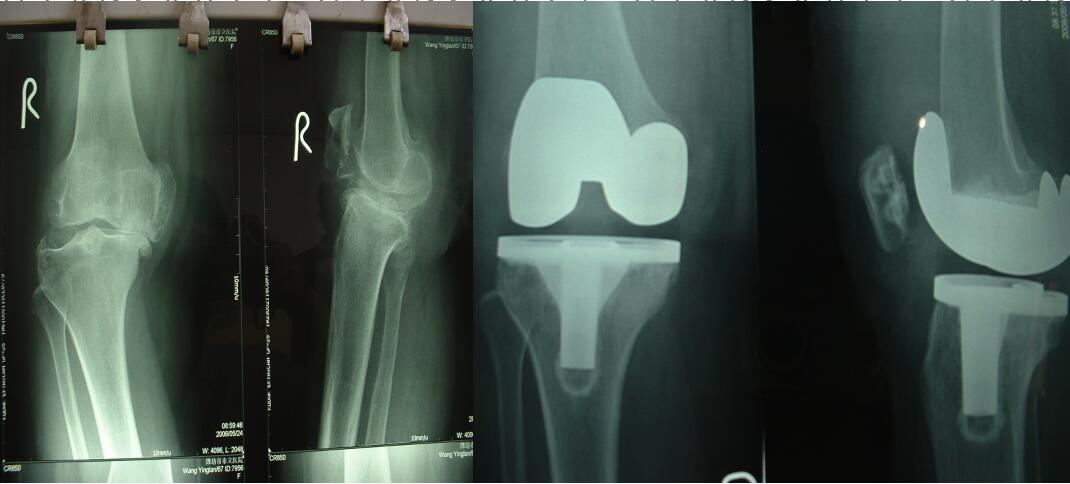

我院一例成功膝關(guān)節(jié)置換手術(shù),圖為患者手術(shù)前后膝關(guān)節(jié)X光片對(duì)比